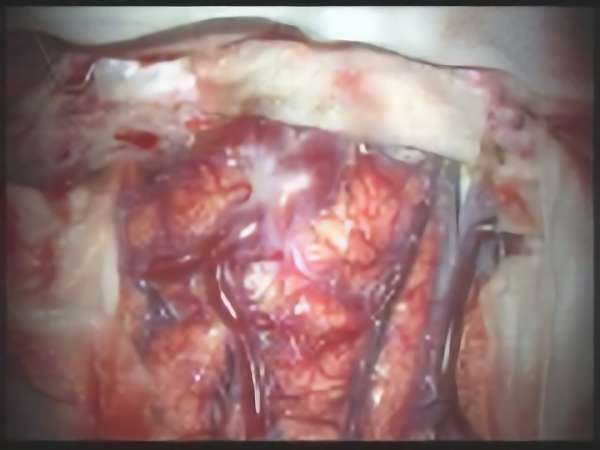

手術写真

手術中